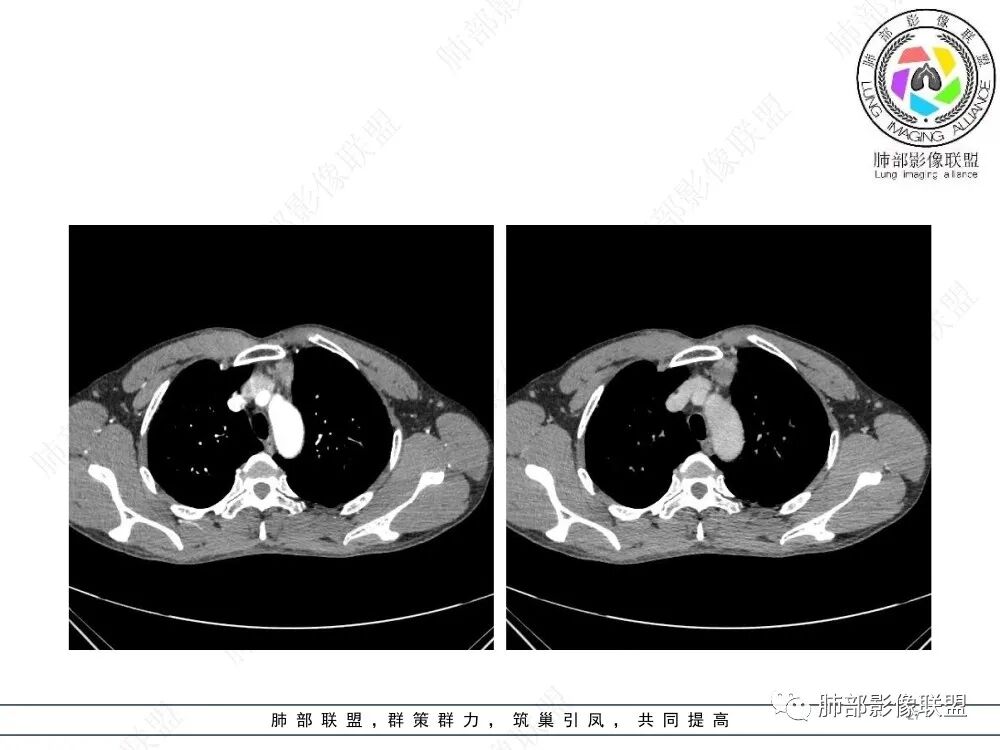

南边:支持前纵隔、胸腺瘤首选,晨读其实定位上还是有点难度,定性常规还是考虑胸腺瘤,其他的几率比较低一些,需要鉴别的是胸膜SFT,神经源性,可惜的是没重建,一直在犹豫胸膜来源的可能性。

谢加平:前纵隔左侧肿块,边界清,强化较均匀,内侧有侵犯脂肪间隙,恶性特点,选胸腺瘤。

2、影像特点:前纵隔偏左侧软组织影,密度相对均匀,未见明显包膜钙化及实质内钙化,局部边缘浅分叶,周围脂肪间隙密度增高、浑浊,未见侵犯大血管、未见纵隔内淋巴结转移、未见侵犯心包内结构、未见胸膜转移结节、未见肿块沿着纵隔胸膜蔓延,未见胸腔积液。增强后动脉期不均匀强化,未见明显纤维分隔。

3、 病 例 小 结:40岁以上,前纵隔偏侧性生长的肿块,常规考虑胸腺瘤。难点就在于胸腺瘤的分型。但是对于前纵隔占位影像诊断的关键在于区分胸腺囊肿、胸腺瘤、胸腺癌及其他恶性肿瘤。至于胸腺瘤,主要在于判断有无侵袭性。